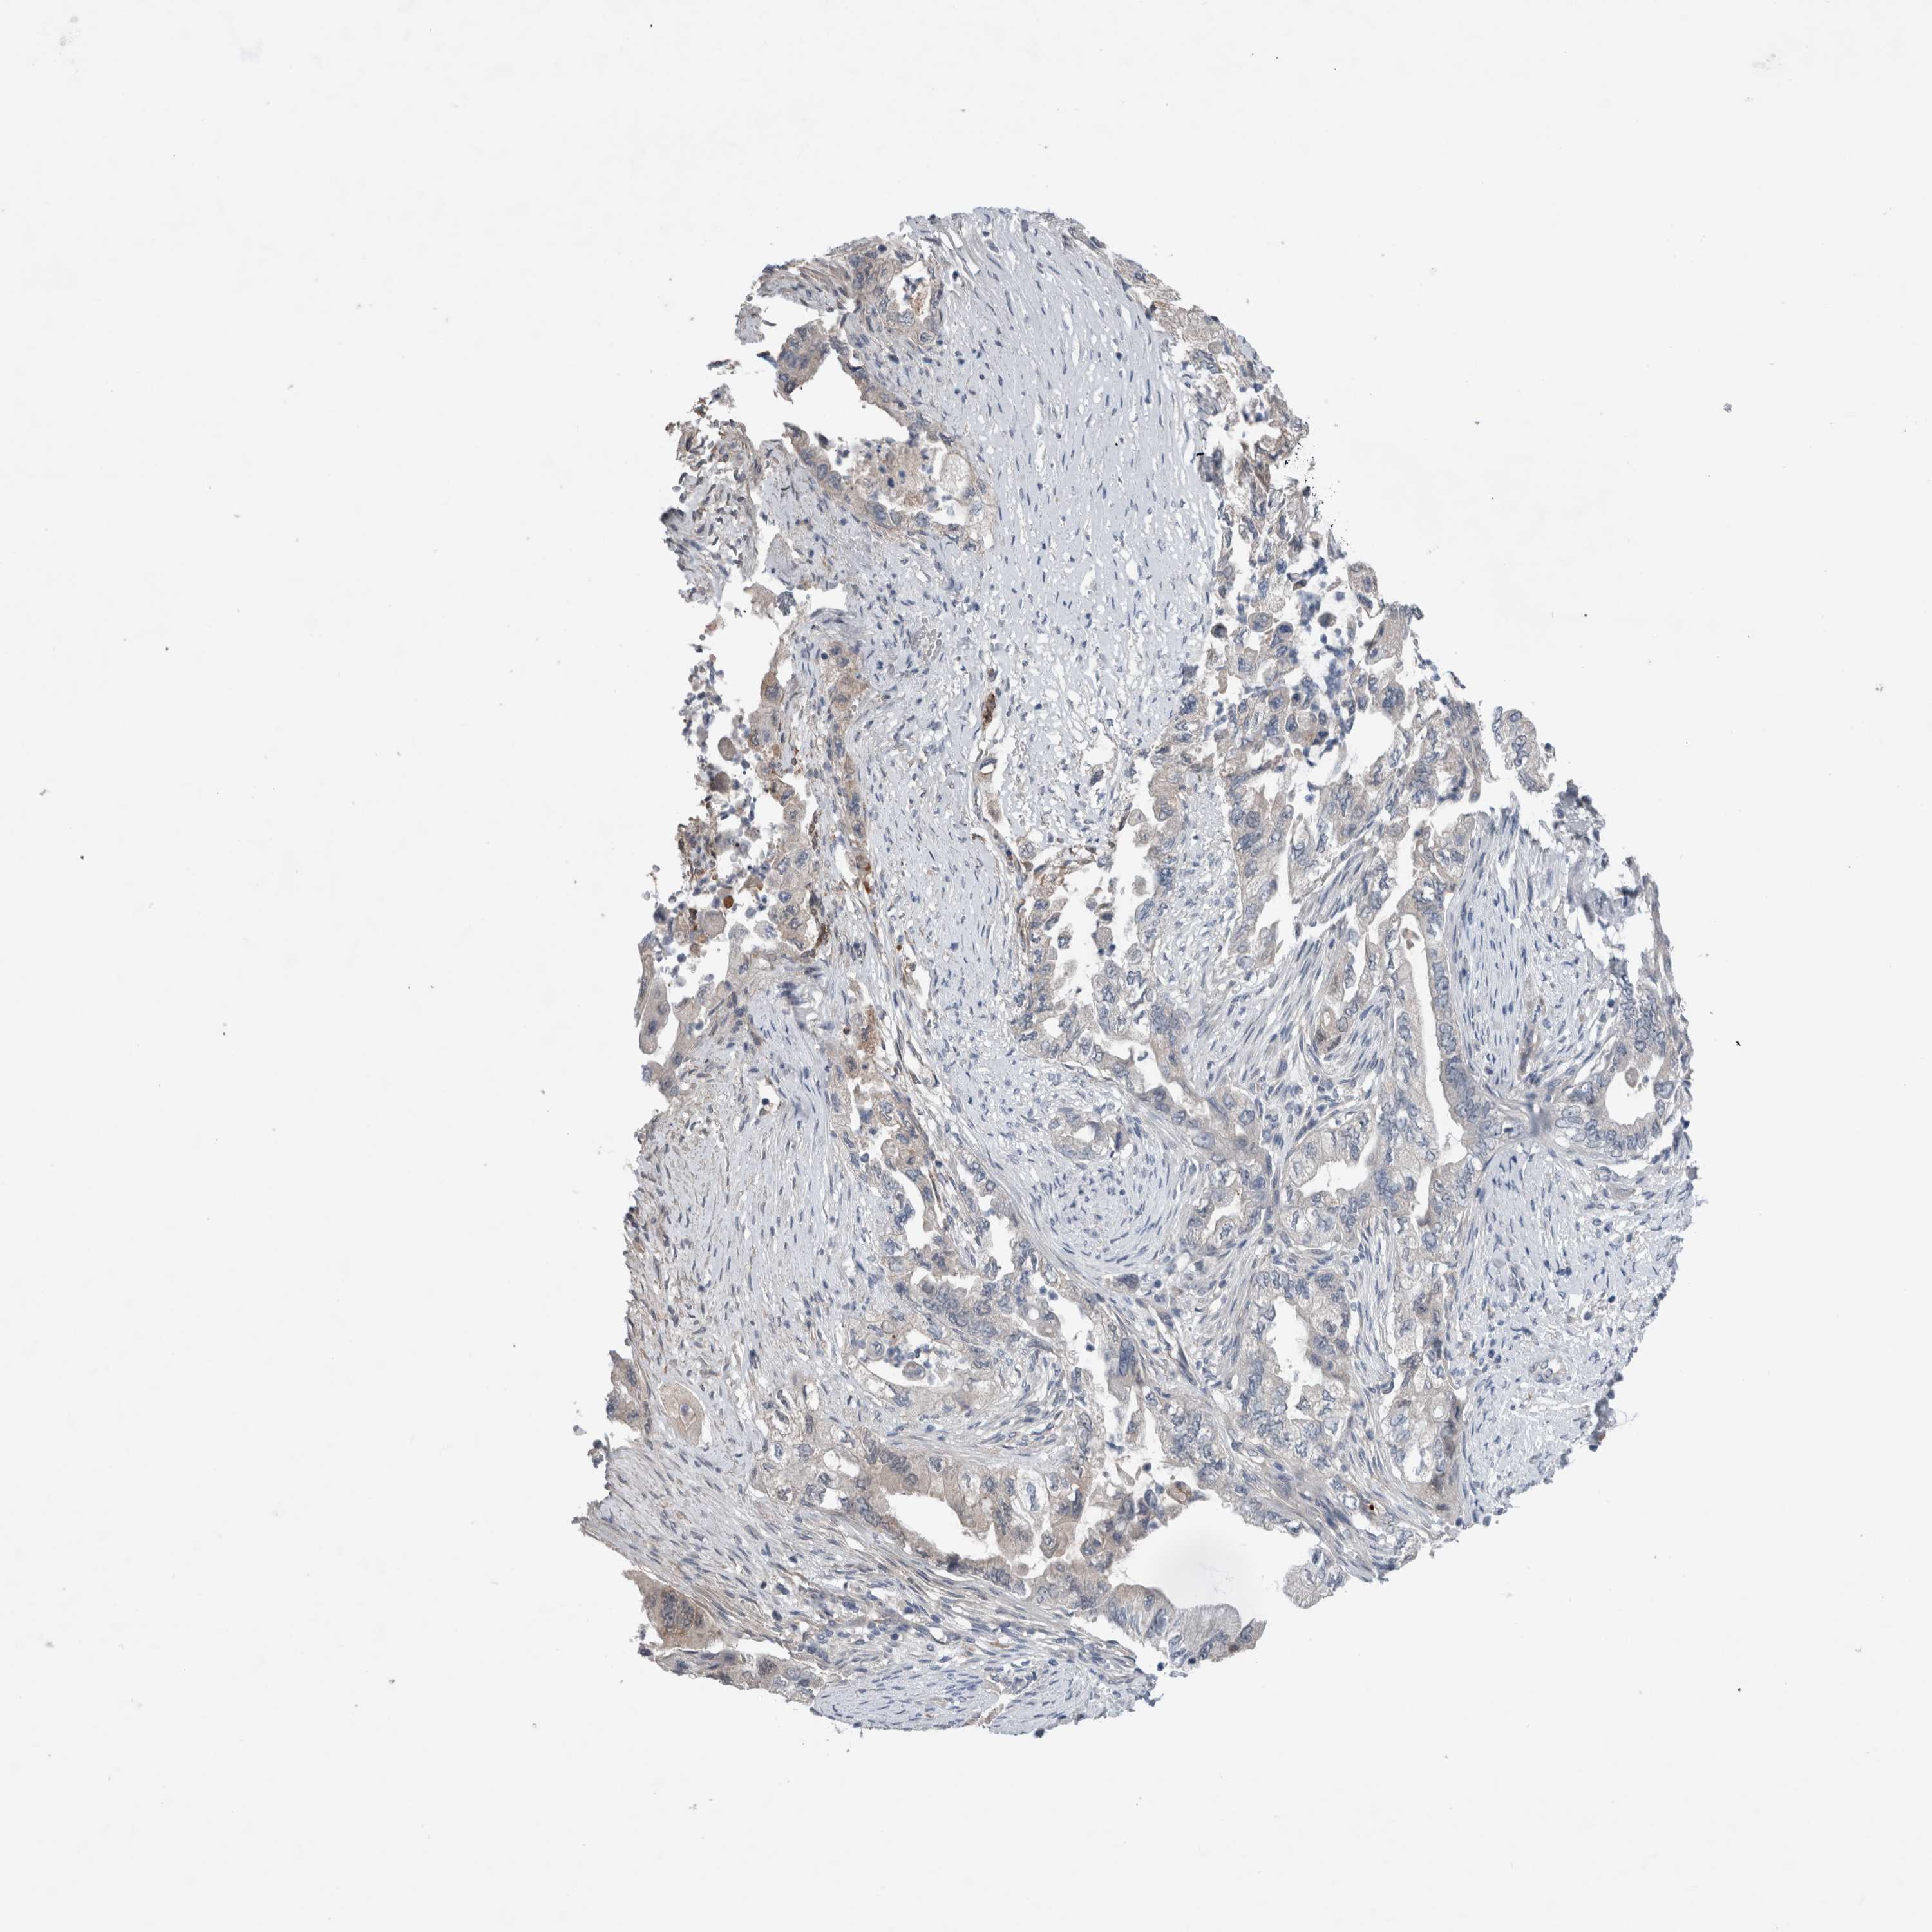

PANCREATIC CANCER - Protein expressioni

A mouse-over function shows sample information and annotation data. Click on an image to view it in a full screen mode. Samples can be filtered based on level of antibody staining by selecting one or several of the following categories: high, medium, low and not detected. The assay and annotation is described here.

Note that samples used for immunohistochemistry by the Human Protein Atlas do not correspond to samples in the TCGA dataset.

Antibody stainingi

Antibody staining in the annotated cell types in the current human tissue is reported as not detected, low, medium, or high, based on conventional immunohistochemistry profiling in selected tissues. This score is based on the combination of the staining intensity and fraction of stained cells.

Each image is clickable and will lead to virtual microscopy that enables deeper exploration of all samples and also displays staining intensity scores, fraction scores and subcellular localization as well as patient and tissue information for each sample.

Antibody HPA024343

Antibody CAB026182

Staining

High

Medium

Low

Not detected

Intensity

Strong

Moderate

Weak

Negative

Quantity

>75%

75%-25%

<25%

None

Location

Nuclear

Cytoplasmic/membranous

Cytoplasmic/membranous,nuclear

Adenocarcinoma, NOS